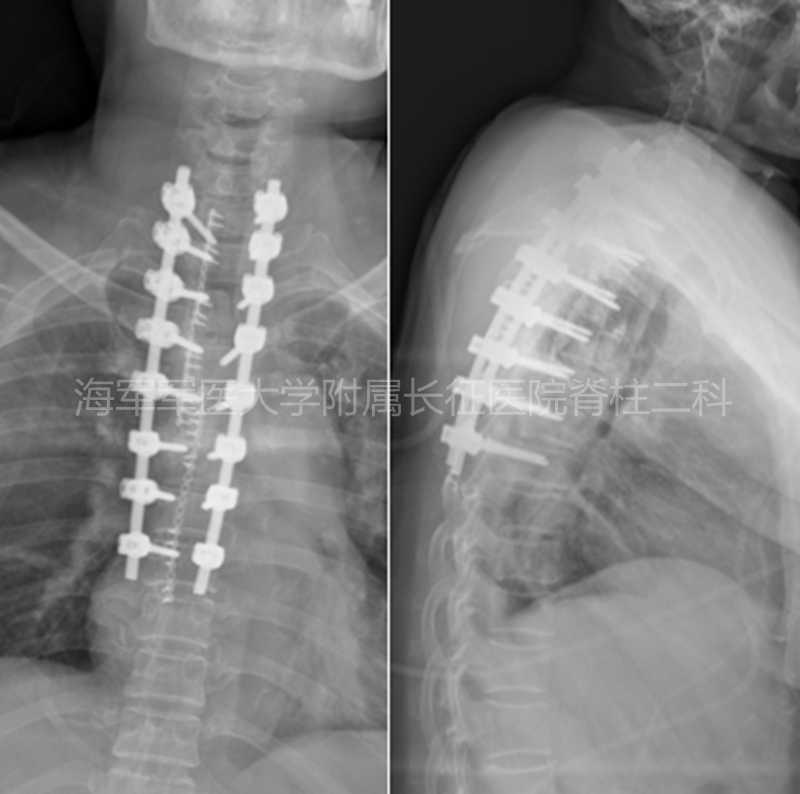

术前、术后侧位平片对比

术前、术后矢状位CT对比

术前、术后水平位CT对比

术前术后矢状位MRI对比

术前术后水平位MRI对比